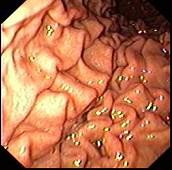

问题 女,28岁,间歇性上腹痛腹胀4年,无呕吐。抗酸制剂治疗无效,查体上腹轻压痛,B超肝查未见异常,胃镜检查如图。最有可能性的诊断是 ( )

选项 A.消化性溃疡 B.胃癌 C.胆囊炎 D.胃下垂 E.萎缩性胃炎

答案 D